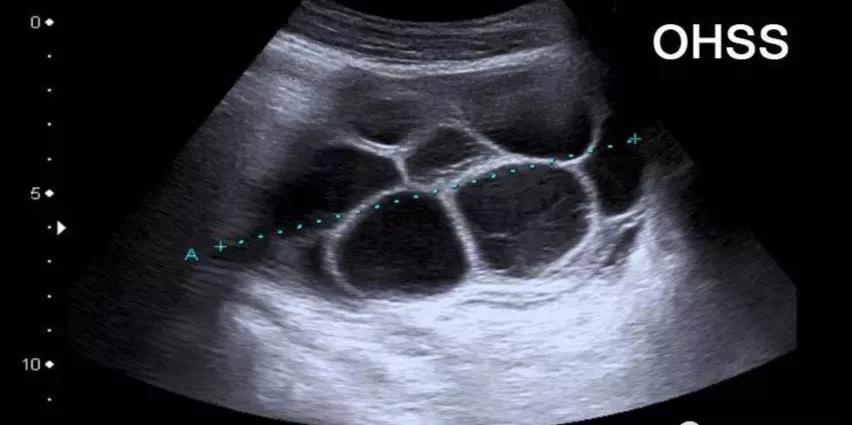

卵巢过度刺激综合征(OHSS)

卵巢过度刺激综合征(OHSS)是在IVF治疗周期中服用注射剂(促性腺激素)可能产生的并发症,表现为卵巢增大、腹胀、胃肠道不适、腹水、少尿及低血容量所致的一系列症候群。但是并非所有接受促排卵治疗的人都会引起卵巢过度刺激综合征,这个和个人对药物的敏感度,自身的内分泌情况,以及促排卵药物的种类和数量等有关系。通过IVF治疗的女性中约有10%会出现卵巢过度刺激综合征。

在试管婴儿治疗过程中,为了促排卵,使用促性腺激素,卵泡生长过程会产生大量雌激素,在促卵泡成熟时要注射绒毛膜促性腺激素(HCG),HCG刺激卵泡产生生长因子(EGF)和一些血管活性物质。孕囊绒毛产生大量HCG,进一步刺激卵泡产生更多的生长因子。这些生长因子通透性增加,血管内的液体部分排到血管外第三腔隙,积累后形成大量腹腔积液和胸腔积液(腹水或胸水)。